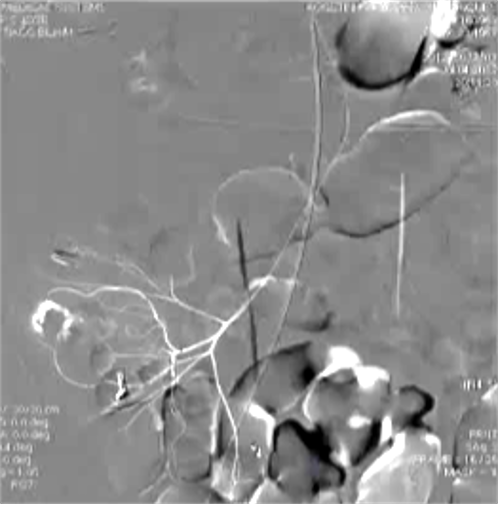

8. 微导管远端栓塞临床意义总结这篇文献的价值在于:1. 提供了历史背景:解释了为什么栓塞技术从“弃用”到“复兴”的关键转折点是微导管技术 2. 给出了扎实的数据:多篇研究证实成功率>80%、肠梗死率接近0% 3. 明确了技术细节:栓塞到什么程度、用什么材料、哪些情况要谨慎(如右结肠/盲肠出血) 4. 确立了地位:微导管栓塞是内镜失败或不适用时,处理严重下消化道出血的首选血管内治疗 为什么远端栓塞?下消化道出血栓塞共轴导管选择使导管到达终末支的位置更满意

1. 有效降低出血动脉灌注压

2. 促进出血血管的痉挛和血栓形成

3. 防止侧支循环参与供血的潜在可能

4. 减少出血邻近肠道缺血

1. 微弹簧栓子,更多的人喜欢用,并非因为效果,主要是安全 弹簧栓子/微弹簧栓子消化道出血栓塞应用

● 弹簧栓子的应用取决于 position of the microcatheter(导管头距出血点距离)

| 弹簧栓子位于直小动脉内 |

消化道出血弹簧栓子远端栓塞

远端栓塞

超选择性栓塞术